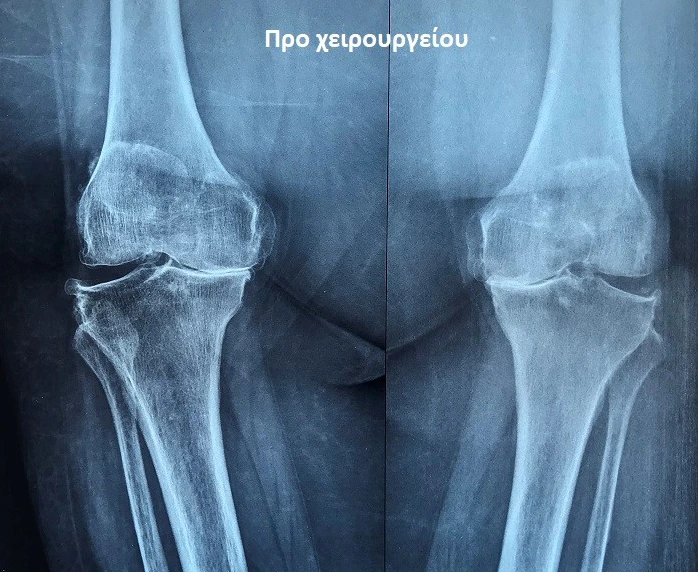

Από το προσωπικό αρχείο του ιατρού